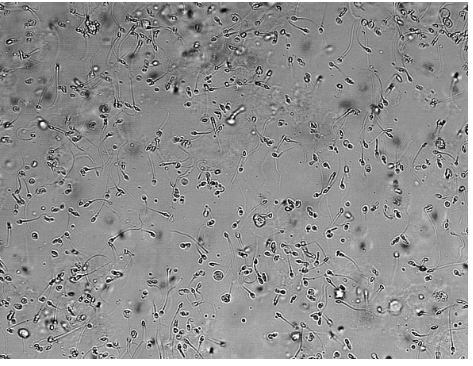

RBCs

Yeast

Aire bubble and oil droplet

WBC 0-8 per field of view is normal

Squamous cells, small centrally located nucleus, most frequent and least significant.

Transitional cells, round or pear shaped, central nucleus, large numbers are unusual and should be reported.

Renal Tubular, relatively large, oblong, eccentric nucleus, large numbers mean tubular necrosis.

Renal tubular cells: collecting ducts, single large nucleus, large number means renal disease often accompanied by increased RBCs

Clue cell, epithelia cell with bacteria on it , usualy vaginal secretions, bacterial vaginosis.

Oval Fat bodies, renal tubular cell containing fat, stain with Sudan III or oil Red O, polarized light see Maltese cross, indicate glomerular dysfunction and renal tubular cell death, increased protein and cast formation.

Sperm, not really a concern but check the age and sex of the patient, young patients it can be sexual abuse.